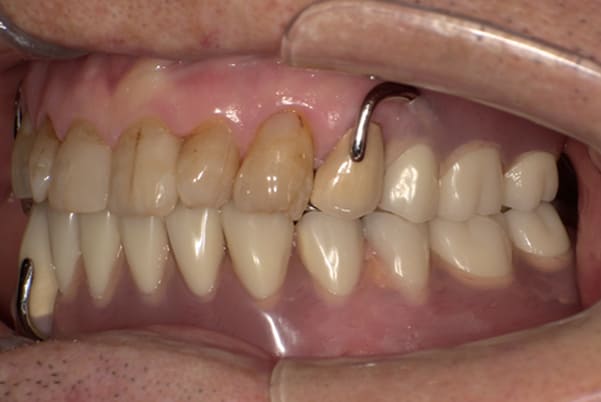

上前歯はブリッジの差し歯により根が折れ炎症を起こしお痛みのある状態でした。

原因は長期使用により下の義歯の歯が削れたことにより、下前歯が上前歯を突き上げ強い力が加わっていたことが根本的な原因と考えられます。

治療前は、奥歯が下がり、かみ合わせが乱れています。適切な入れ歯はそのままのかみ合わせで義歯を作るのではなく治療後のように、前歯から奥歯までのラインが真っすぐ揃った、かみ合わせの面を適切に付与し、よく咬め、残りの歯に負担がかからないかみ合わせとしました。

治療前の入れ歯の奥歯は、治療後の義歯と比較しても分かるように、歯が削れ平らになった状態です。

これにより奥歯のかみ合わせは低くなり、前歯のみが強くあたり、かみ合わせにより上の前歯大きな負担がかかっていたことにより、上の前歯が折れたことが考えられます。